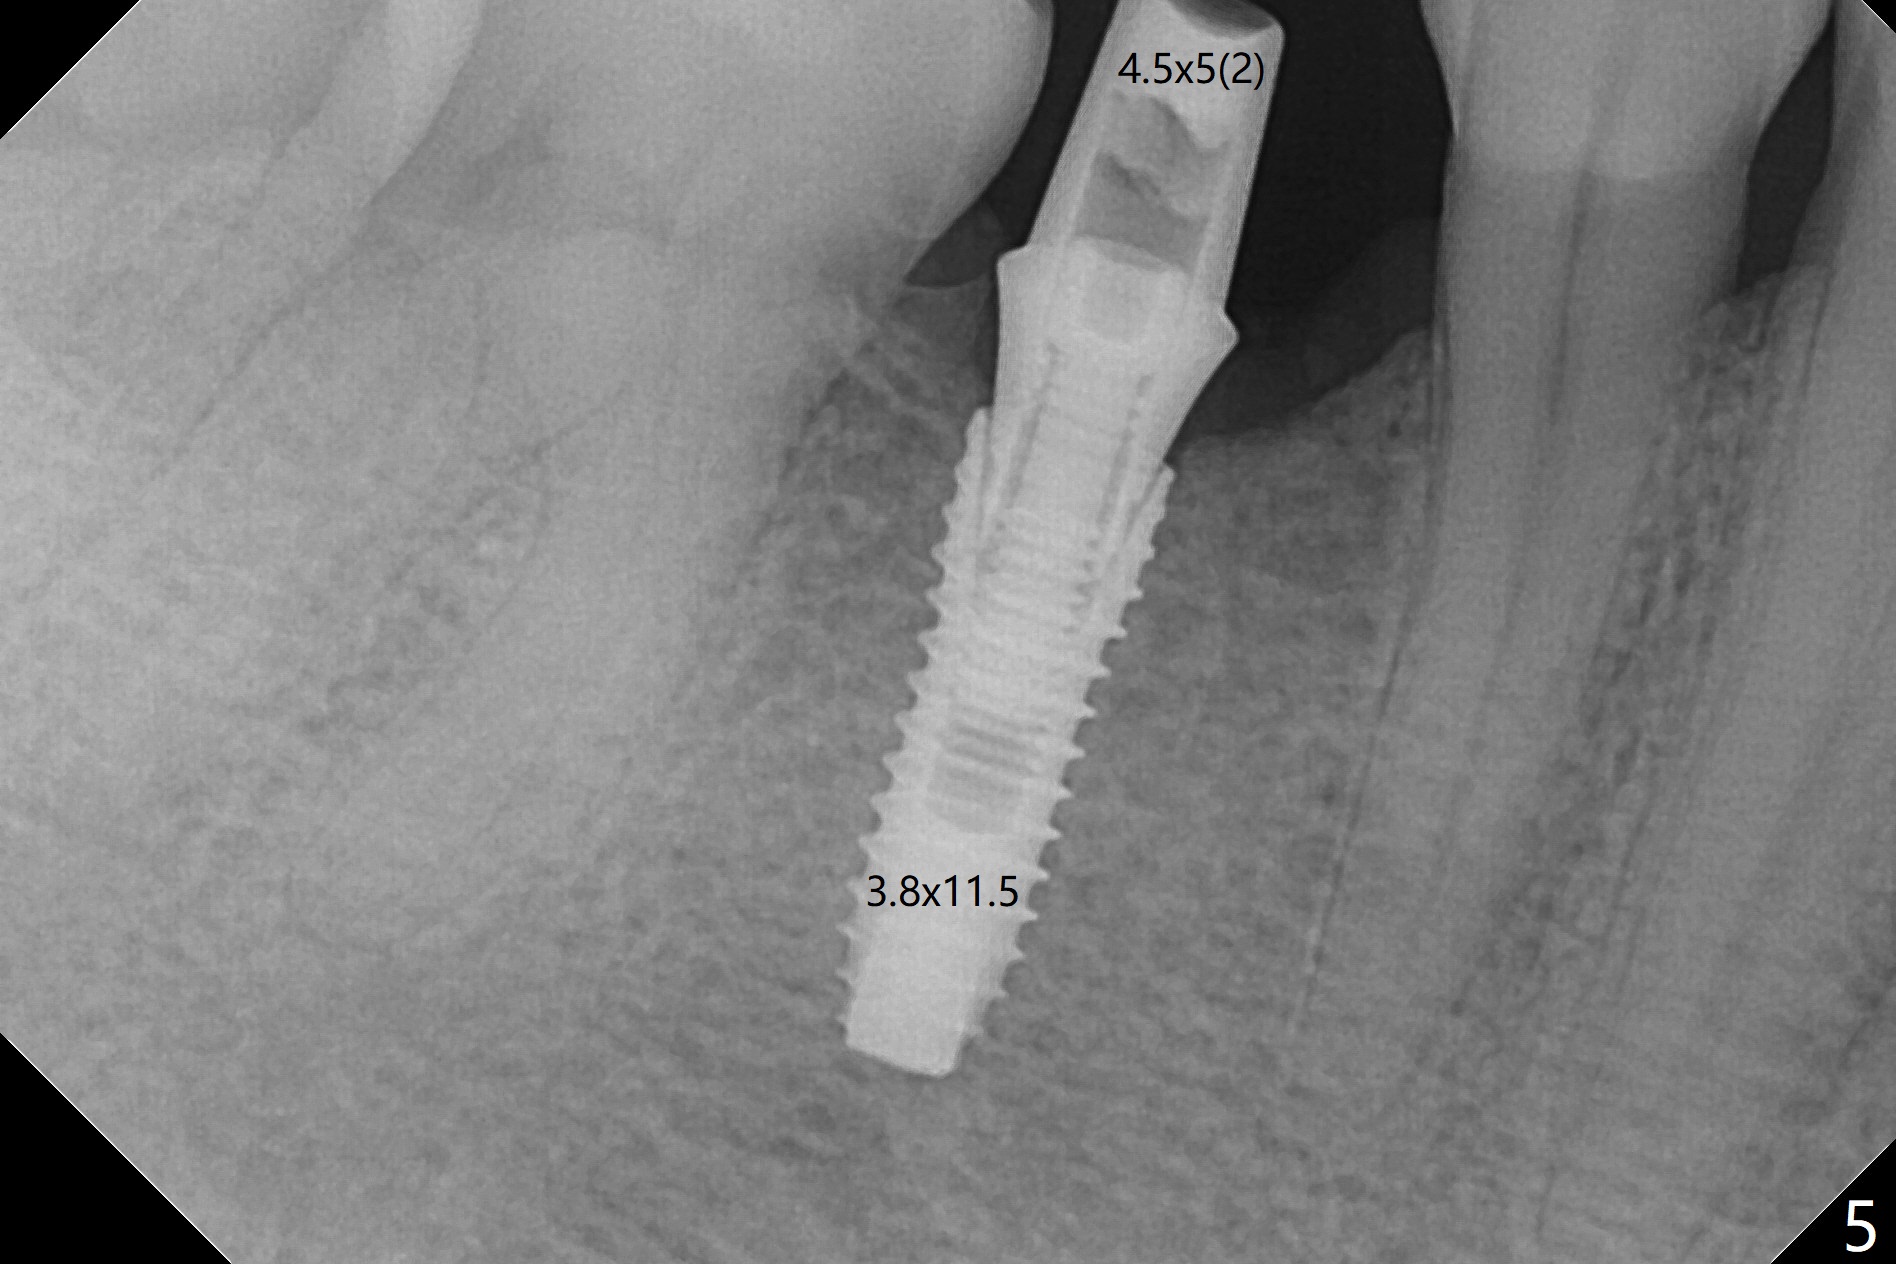

The base of the edentulous ridge at #29 looks wide (Fig.1), but the most coronal portion is the thin soft tissue (Fig.2).  It appears that there has been bone resorption since extraction.  The initial osteotomy depth is 11.5 mm (Fig.3).  Since the Mental Loop seems to be nearby, the depth of subsequent osteotomy (3 mm) remains the same (Fig.4).  Although the final depth of osteotomy is 13 mm, the implant placed is short (3.8x11.5 mm, Fig.5,6), as compared to the immediate implant (3.8x18 mm) at the contralateral side (#20).  There is mild bone resorption mesially 4 months postop (Fig.7).  The crown is loose (poor osteotomy position, guide necessity) 7 months post cementation immediately prior to 18 cementation, although there is no gross bone losss 1 year 7 months post cementation (Fig.8).